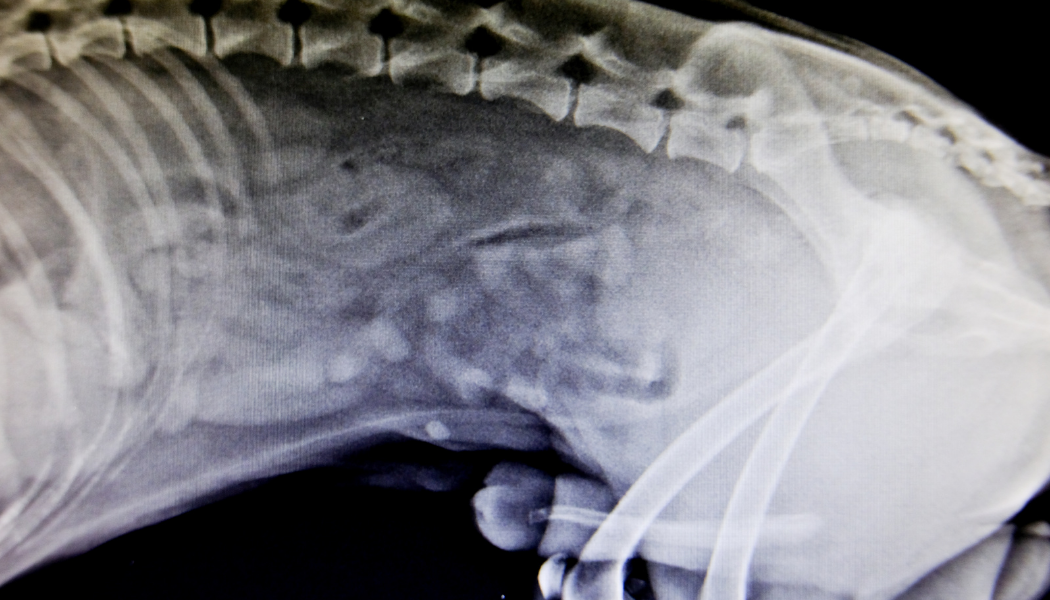

Epilepsy is the most common neurological presentation in veterinary practice, and despite the amount of antiepileptic drugs available on the market, many of our patients continue to suffer a high number of seizures that can affect the quality of life of both the patient and the owner. Epilepsy should be considered as the clinical manifestation of a multifactorial disease of the brain and therefore its treatment could also be considered multimodal. The ideal treatment should be individually focused on the patient including antiepileptic medication, an appropriate nutrition plan and identify possible environmental/stress factors that might be involved in epileptic seizures. During this talk we will talk about those parts of epilepsy treatment that go beyond medications and therefore include diet, possible environmental factors, and vagal nerve stimulation.